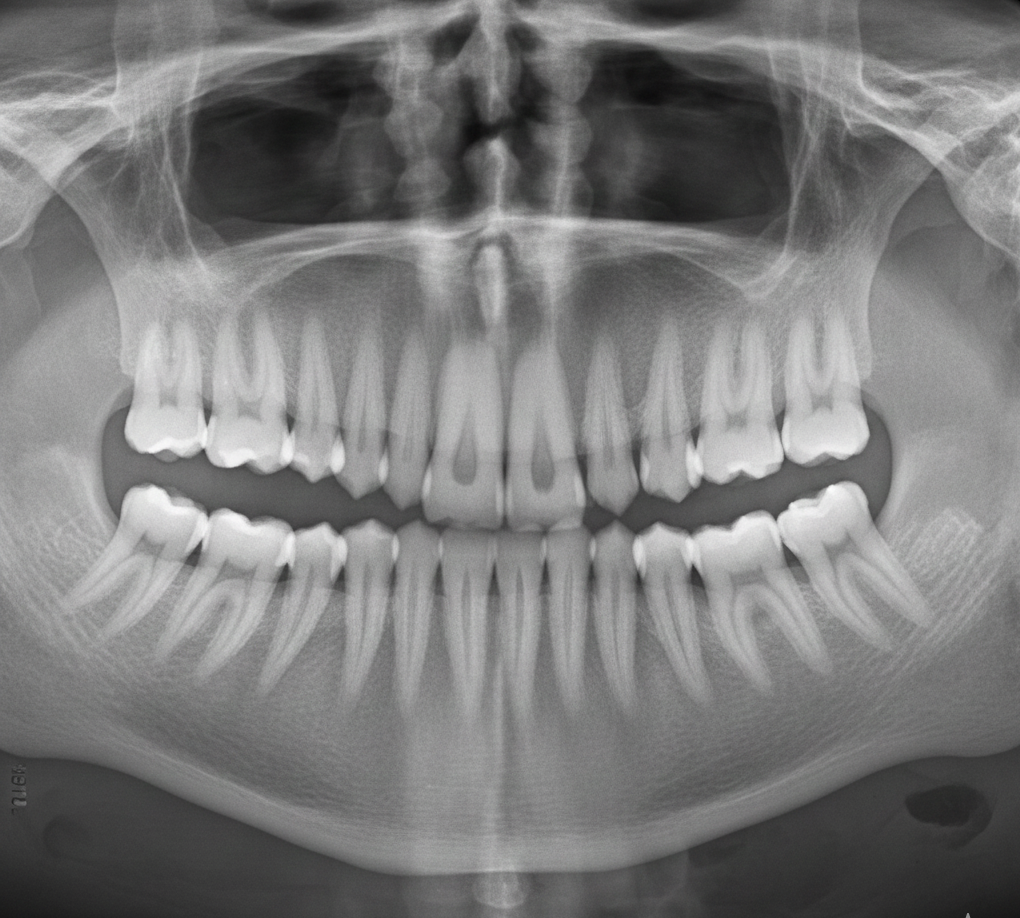

Valoración digital previa

Antes de cualquier intervención, realizamos un estudio completo utilizando radiografía 3D. Esta tecnología nos permite ver con precisión la posición de la muela, su relación con el hueso, los tejidos cercanos y el resto de dientes. Gracias a este diagnóstico detallado, planificamos un procedimiento seguro, predecible y adaptado a cada caso, reduciendo tiempos de intervención y molestias posteriores.